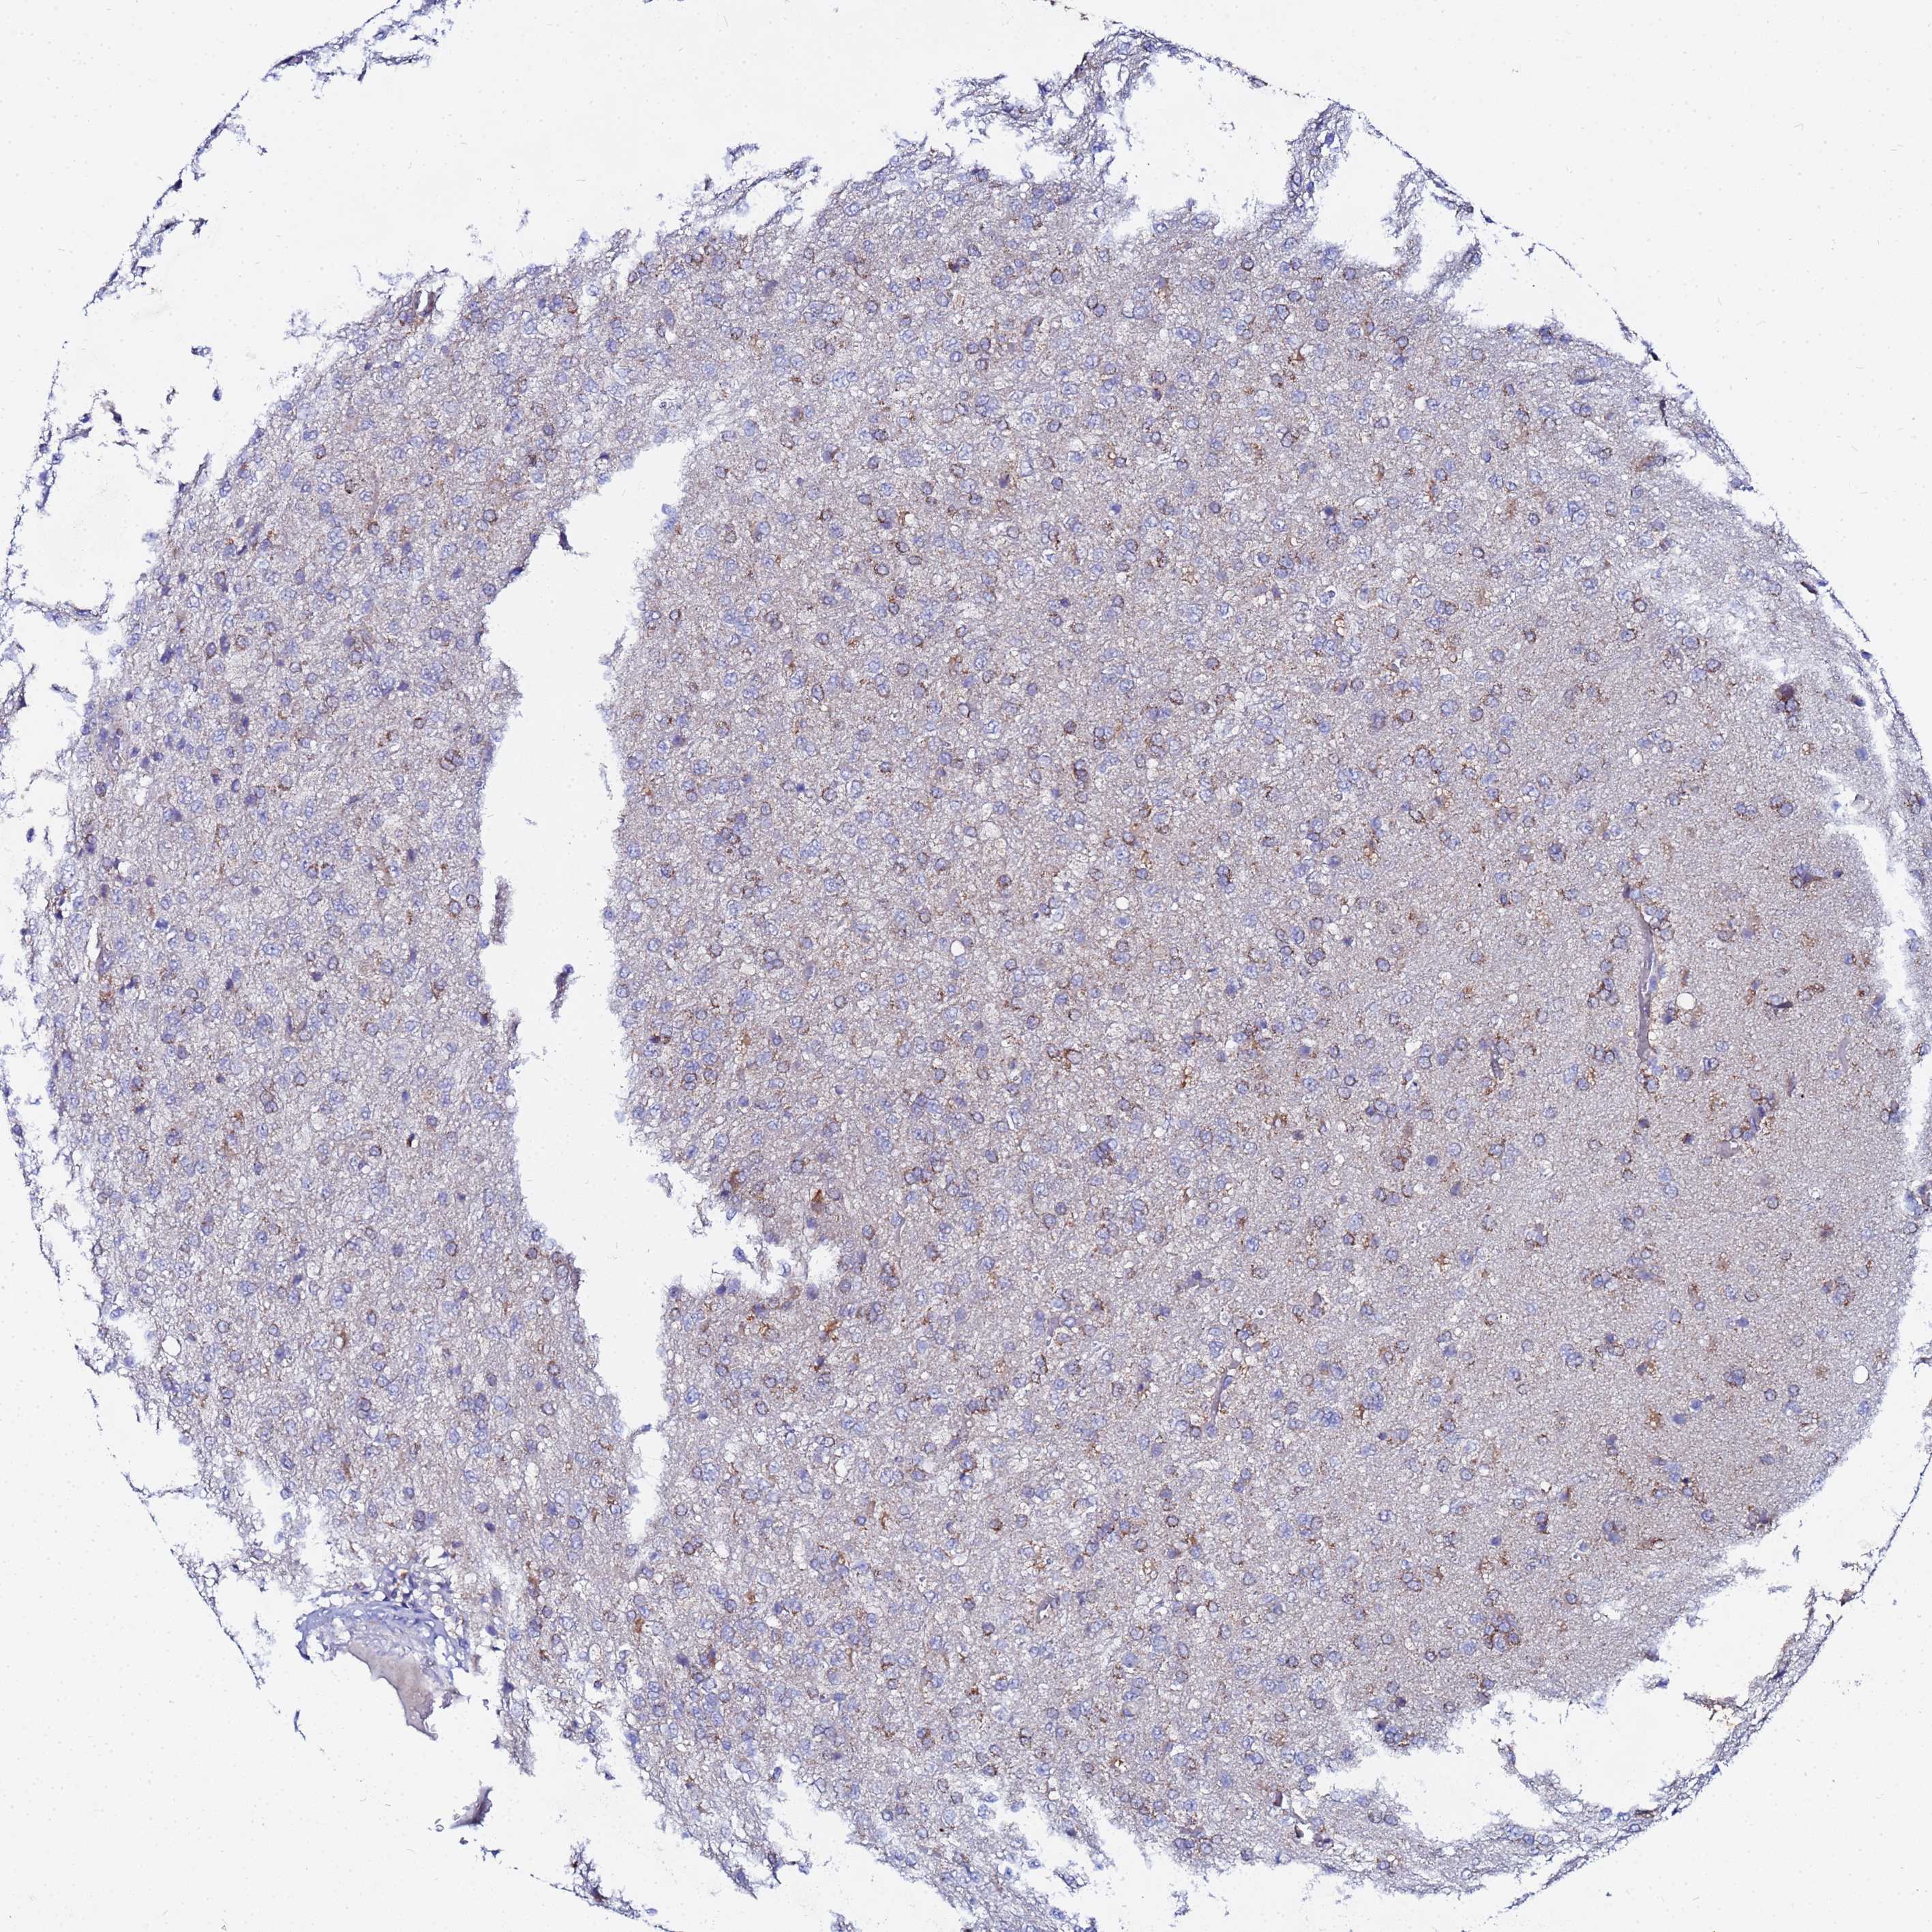

GLIOMA - Protein expressioni

A mouse-over function shows sample information and annotation data. Click on an image to view it in a full screen mode. Samples can be filtered based on level of antibody staining by selecting one or several of the following categories: high, medium, low and not detected. The assay and annotation is described here.

Note that samples used for immunohistochemistry by the Human Protein Atlas do not correspond to samples in the TCGA dataset.

Antibody stainingi

Antibody staining in the annotated cell types in the current human tissue is reported as not detected, low, medium, or high, based on conventional immunohistochemistry profiling in selected tissues. This score is based on the combination of the staining intensity and fraction of stained cells.

Each image is clickable and will lead to virtual microscopy that enables deeper exploration of all samples and also displays staining intensity scores, fraction scores and subcellular localization as well as patient and tissue information for each sample.

Antibody HPA042145

Antibody HPA044987

Antibody CAB045971

Antibody CAB045972

Staining

High

Medium

Low

Not detected

Intensity

Strong

Moderate

Weak

Negative

Quantity

>75%

75%-25%

<25%

None

Location

Nuclear

Cytoplasmic/membranous

Cytoplasmic/membranous,nuclear

Glioma, malignant, Low grade

Glioma, malignant, High grade